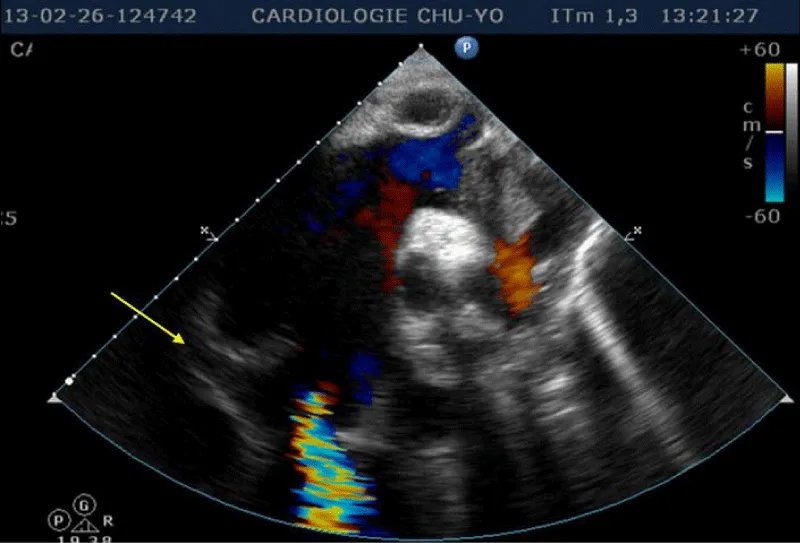

Laboratory examination reported a hemoglobin level of 12.2 g/dl with normal platelets and white blood cells count; Kidney function test and blood electrolytes were normal; the cycle of serum troponin and creatinine-phosphokinase levels were normal; HIV retroviral serology was negative. Chest x-ray reported a cardiomegaly (cardiothoracic index of 0.6) with pulmonary edema and an enlarged upper right arch of the mediastinum (Figure 1). A transthoracic electrocardiogram recorded regular sinus tachycardia (110 cycles per minute), left anterior hemiblock and poor progression of R waves in the anterior leads (Figure 2).

Figure 1: Frontal chest x-ray showing global cardiomegaly with signs of cardiac lung and enlargement of the upper mediastinum with overhang of the right upper arch.